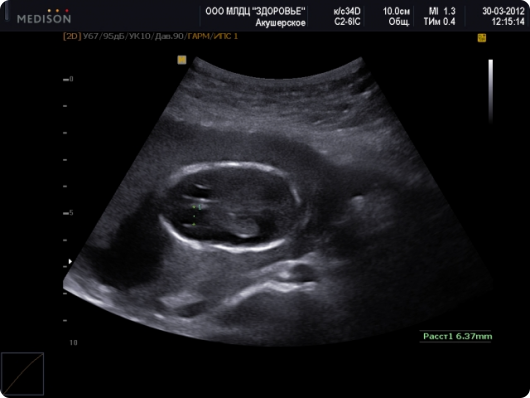

Маловодие при беременности встречается примерно у 5 из 100 женщин. Причем проявляется оно как у первородящих, так и повторнородящих независимо от возраста. Данный диагноз ставится на основании результатов УЗИ, по которым высчитывается индекс амниотической жидкости (ИАЖ):

| ИАЖ | диагноз |

| 5-8 см | норма |

| 2-5 см | умеренное маловодие |

| менее 2см | выраженное маловодие |